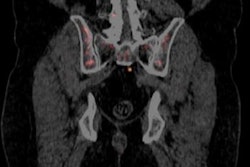

Radiation oncology firm Varian Medical Systems said Moinhos de Vento Hospital is the first cancer center in Brazil to begin using its Calypso system.

The system was used with a Varian TrueBeam medical linear accelerator to treat a prostate cancer patient on January 10, Varian said. Calypso can detect slight movements of a tumor, enabling it to be targeted accurately with the treatment beam.

The Calypso beacon system implants transponders into the tumor that emit nonionizing electromagnetic signals; these signals are tracked in real-time and used to keep a treatment beam on target.